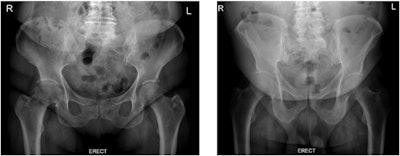

To address these challenges, the group tested whether radiation dose and image quality differ between two different erect pelvic radiographic procedures -- those with and without the displacement of anterior adipose tissue.

In the group of patients using the fat displacement protocol, a statistically significant reduction in waist circumference (4.7%), dose area product (38.5%), entrance surface dose (44%), and effective dose (38.7%) were observed (p < 0.05), according to the findings.

"Image quality was generally better when patients had fat tissue displaced from the region of interest, as body part thickness decreased, resulting in improved contrast resolution and lower noise levels," the group wrote.